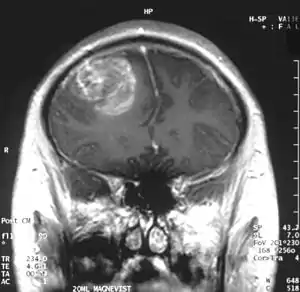

Diagnóstico

Quando visto através da ressonância magnética, os glioblastomas frequentemente aparecem como lesões com realce em anel. No entanto, esta aparência não é específica, já que outras lesões como abscessos, metástases e esclerose múltipla tumefativa podem ter uma aparência similar.[12]

O diagnóstico definitivo do glioblastoma multiforme requer uma biópsia estereotática ou uma craniotomia com ressecção do tumor e confirmação patológica.